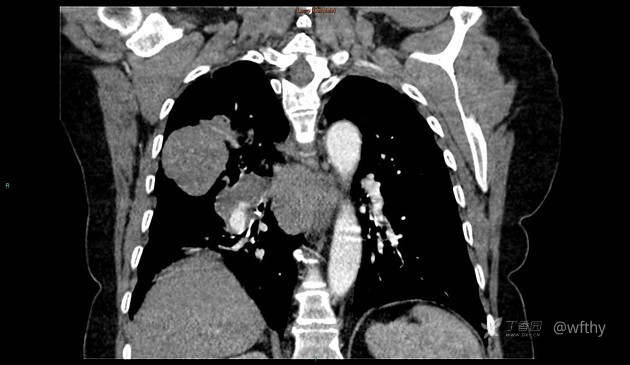

病例女65,头部肿块